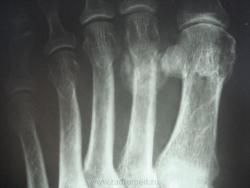

женщина обратилась с жалобами к участковому терапевту на боли во 2 и 3 пальцах правой стопы, предварительный диагноз у них как всегда " артроз", про травму ничего не пишут в амбулаторной карте, как внешне выглядит стопа тоже не описывают. Может ли это быть патологическим переломом????

Перелом по типу маршевого, но так как на фоне минералопении - это ближе к Лоозера, чем Дойчлендера...

Патологическая перестройка от перенапряжения может возникать в разных костях, однако наиболее типичные места – дистальный отдел 2-й или 3-й (реже) плюсневых костей и проксимальный метафиз большой берцовой кости. Первая локализация носит название в литературе как «маршевая стопа», перелом Дойчлендера, усталостная стопа и др. и встречается чаще у солдат-новобранцев. Перестройка большой берцовой кости встречается чаще у спортсменов в период интенсивных тренировок.

На рентгенограммах выявляется локальная периостальная реакция в виде одно- или многослойного периостоза. Соответственно ему в костномозговом канале появляется склероз, сужающий просвет канала. В кортикальном слое и среди склероза видна полоска просветления, чаще имеющая клиновидную форму- собственно « ползучий » перелом. При продолжении действии нагрузки он постепенно увеличивается. Однако если травмирующий фактор прекращает свое действие, достаточно быстро восстанавливается нормальная структура кости.

Это остеохондропатия диафиза II плюсневой кости (б-нь Дойчлендера).